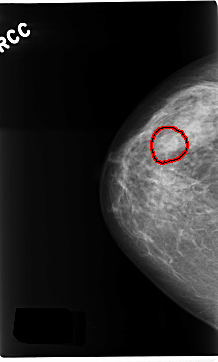

FILE: C_0229_1.RIGHT_MLO.OVERLAY

TOTAL_ABNORMALITIES 1

ABNORMALITY 1

LESION_TYPE MASS SHAPE OVAL MARGINS CIRCUMSCRIBED

ASSESSMENT 3

SUBTLETY 5

PATHOLOGY BENIGN

TOTAL_OUTLINES 1

BOUNDARY